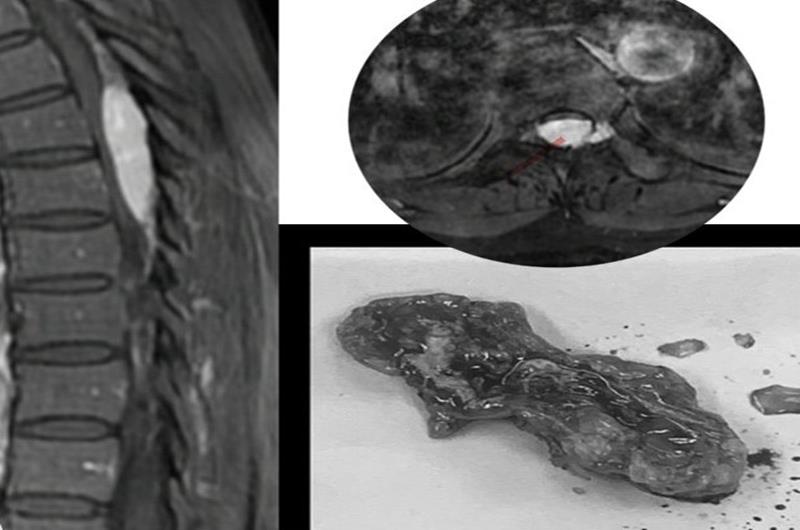

ThS.BS Nguyễn Xuân Hùng, chuyên khoa Ngoại thần kinh cho biết, bệnh nhân là T.T.C, 47 tuổi , ngụ xã Bình Sơn, H.Long Thành, vào viện vì yếu 2 chân, không đi lại được, tê vùng bụng xuống 2 chân. Sau khi nhập viện Khoa Cấp cứu, được các bác sĩ khám, chỉ định chụp MRI cột sống, phát hiện u tủy sống ngực chèn ép tủy nặng. Bệnh nhân đã được các bác sĩ khoa Ngoại thần kinh phẫu thuật ngay lấy toàn bộ khối u, giải phóng chèn ép tủy, lấy mẫu u làm giải phẫu bệnh lý. Sau mổ 5 ngày, bệnh nhân được tập vật lý trị liệu bổ sung và đã có thể đứng được, đi lại được.

Khối u chèn ép tủy được lấy ra khỏi cơ thể cho bệnh nhân